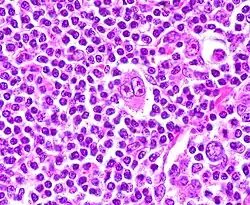

Клетки Березовского — Рид — Штернберга

Клетки Березовского — Рид — Штернберга — атипичные многоядерные гигантские клетки, пролиферация которых характерна для лимфогранулематоза[1].

Чаще всего образуются из В-клеток, присутствующих в герминативном центре или покинувших его. Одной из особенностей этих клеток является высвобождение ими факторов, индуцирующих накопление реактивных лимфоцитов, макрофагов и гранулоцитов, составляющих обычно более 90 % общего количества опухолевых клеток. Типичной формой клеточной гибели для этих клеток является мумификация[2].

- Диагностические клетки: крупные (диаметром ≥ 45 мкм), много- или одноядерные, состоят из нескольких долей, содержащих «штампованные» ядрышки размером 5-7 мкм, имеют обильную цитоплазму.

- Мононуклеарные клетки: содержат одиночное ядро с большим, похожим на включение ядрышком.

- Лакунарные клетки: содержат складчатое или многодольчатое ядро, обильную бледную цитоплазму, которая часто утрачивается в процессе приготовления срезов и ядра остаются в пустой полости (лакуне).

- Лимфогистиоцитарные клетки: имеют полиплоидные ядра, плохо различимое ядрышко, умеренно обильную цитоплазму («кукурузные» клетки).